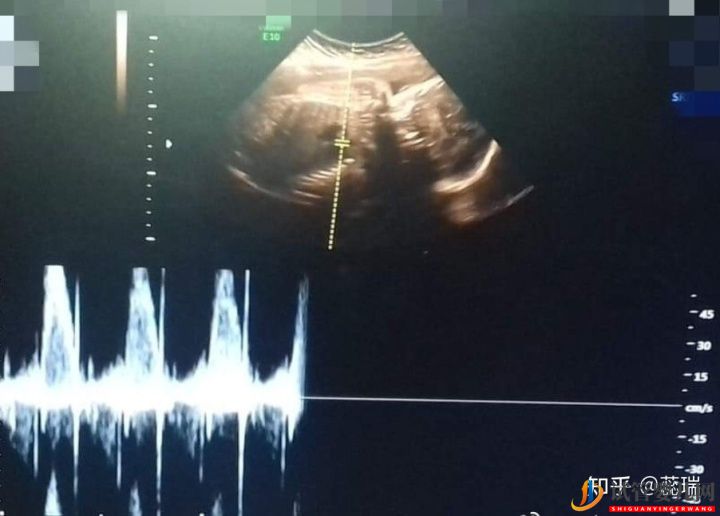

根據(jù)每人情況不同,用藥天數(shù)會不同,這期間通過驗血和陰道B超監(jiān)測卵泡發(fā)育情況,如果卵泡發(fā)育成熟,會打夜針,防止卵泡排出,把卵泡鎖住,固定卵泡,準備取卵,取卵同時男方取精,所以一般在打夜針之前男方應(yīng)該儲存精子,(7天之內(nèi)的精子質(zhì)量最好)